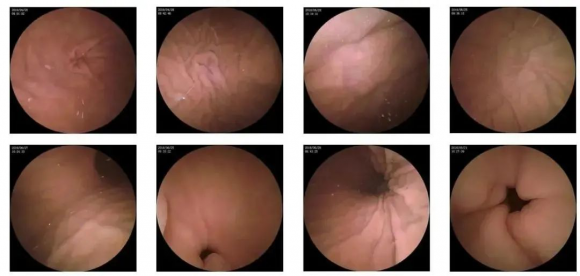

10—15分钟即可完成贲门、胃底、胃体、胃角、胃窦、幽门等解剖部位观察,让胃部检查更高效。更为重要的是,检查全程不痛、没创、无麻醉,避免了传统插管胃镜带来的生理痛苦。

二、高清图像,精确诊断

胶囊机器人的专利三镜片镜头,可深入观察0.04毫米微小单位,每秒可拍高达4张高清医学照片。

医生通过智能阅片系统,可自动对海量图像识别过滤,智能筛选,能有效提升医生检查及阅片效率。

任何细微的胃部病变,如胃溃疡、胃出血、息肉等都无所遁形,尽在磁控胶囊式内窥镜系统的掌握之中。